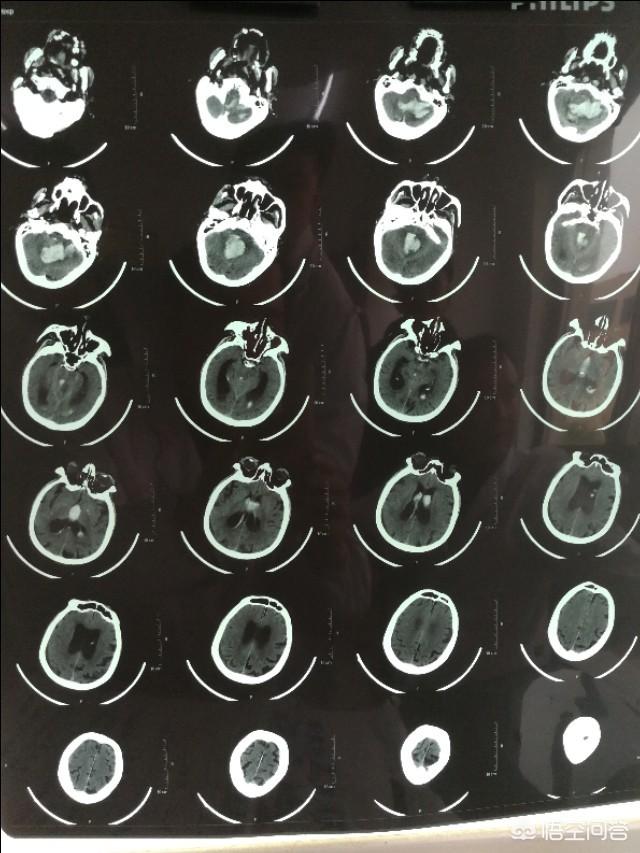

脳出血には脳実質出血とくも膜下出血がある。

脳実質出血は、高血圧性脳出血、血管アミロイドーシス出血、動静脈奇形出血によく合併する。

脳出血は、非外傷性因子による脳実質内の出血であり、最も一般的なものは高血圧性脳出血である。

長期にわたる高血圧はしばしば脳の小動脈の動脈硬化を引き起こし、糖尿病などの他の要因も小動脈病変を引き起こし、その上で急激な血圧上昇が脳動脈の破裂を引き起こす。

脳出血は一般に脳実質出血とくも膜下出血に分けられる。前者には一般的に高血圧性脳出血、血管アミロイドーシス出血、動静脈奇形出血が含まれる(これは通常治癒後に再発することはない)。